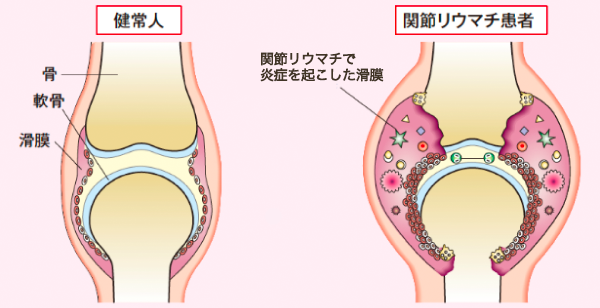

関節リウマチは原因不明の自己免疫疾患で関節以外に脊椎、腎臓、皮下組織などにも病巣が広がる全身性炎症性疾患です。

原因は遺伝が40%、環境因子が60%と言われています。環境因子とは感染、けが、妊娠、出産などがあります。免疫系が過剰に働くことにより関節内に炎症が起きて滑膜細胞が増殖し痛みや腫れを起こし軟骨や骨を破壊していきます。

関節リウマチの進行機序

初期は炎症性滑膜炎による痛みと腫れです。進行すると滑膜炎が悪化しパンヌスを形成し軟骨を浸食し骨が破壊され変形性関節症が進みます。通常の変形性関節症と異なるのは関節全体が一様に破壊されてくるため強い変形を来しやすいのが特徴です。